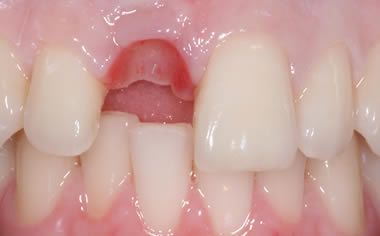

More front teeth replaced by dental implants

Case Three (4 images)